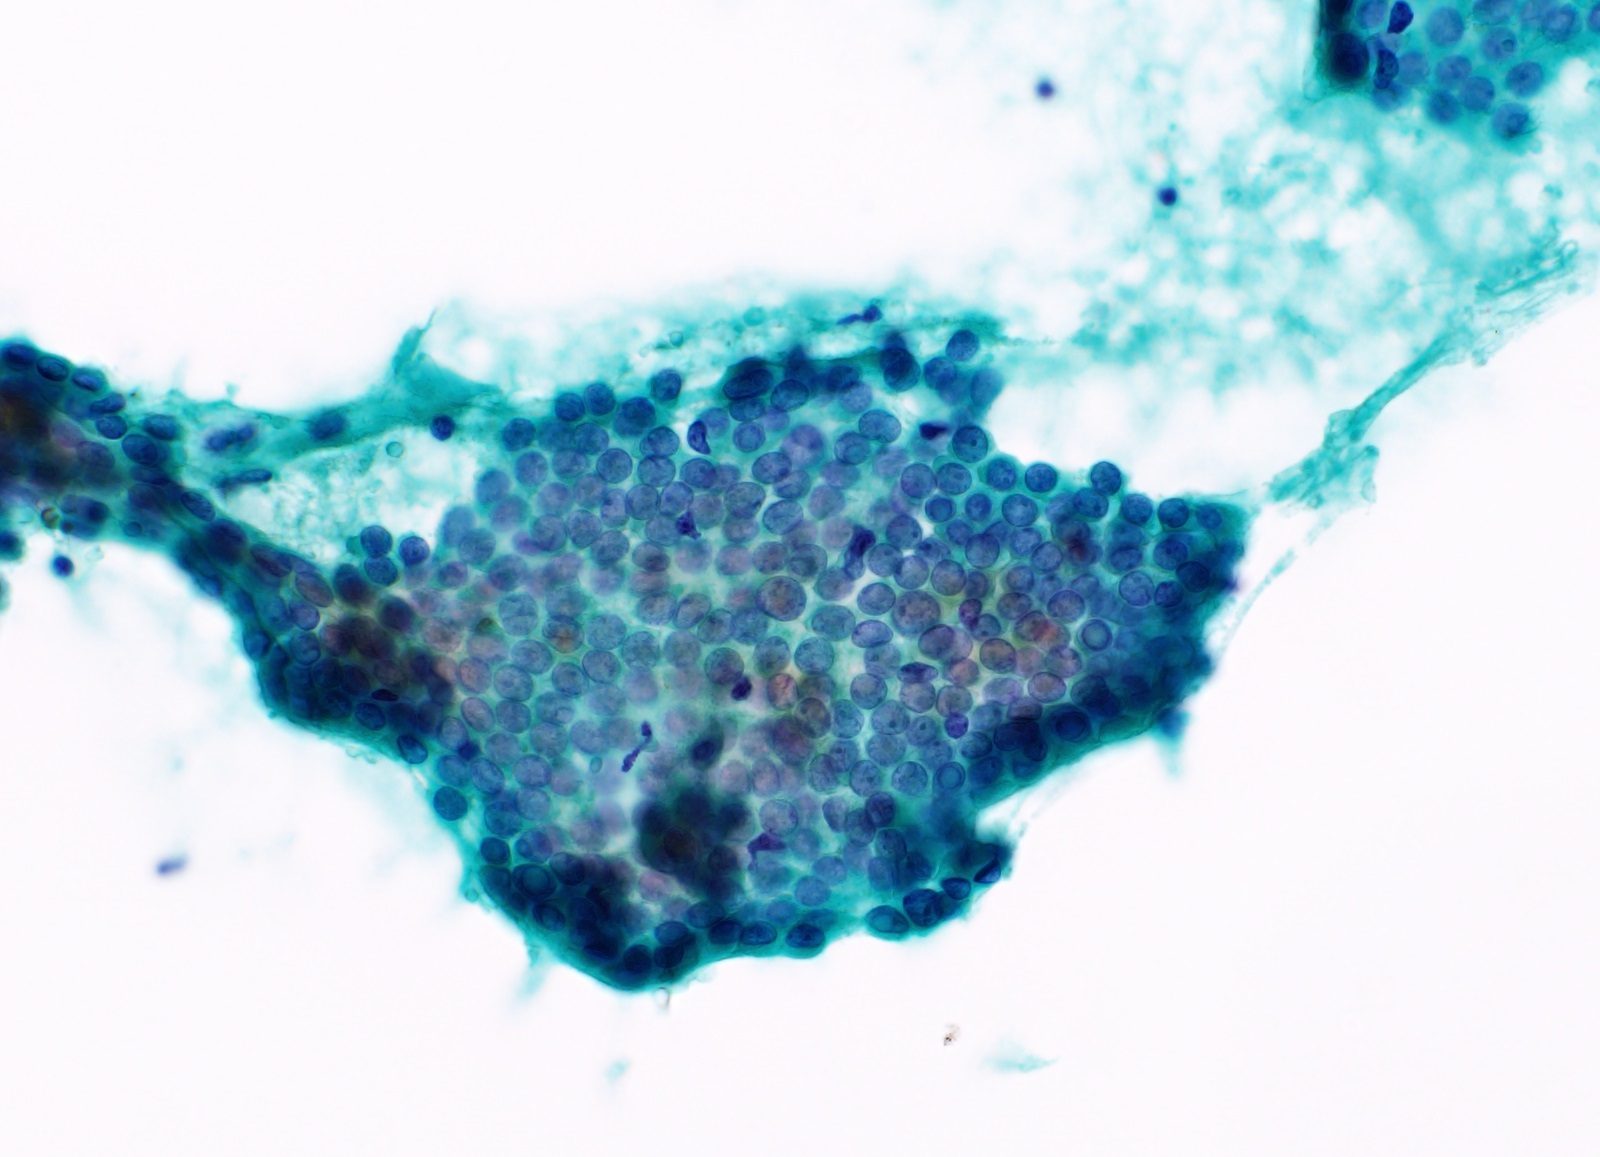

卵巣漿液性癌

【細胞像】

- 球状ないし乳頭状集塊が出現し、集塊内に砂粒小体を認めることもある。

- 腫瘍細胞は多彩性を欠き均一であり、ライトグリーンに淡く染まる。

- 核は類円形を示すが異型が強い、核縁は肥厚する。

- 核クロマチンは微細顆粒状に分布する。

- 1~数個の核小体を認める。